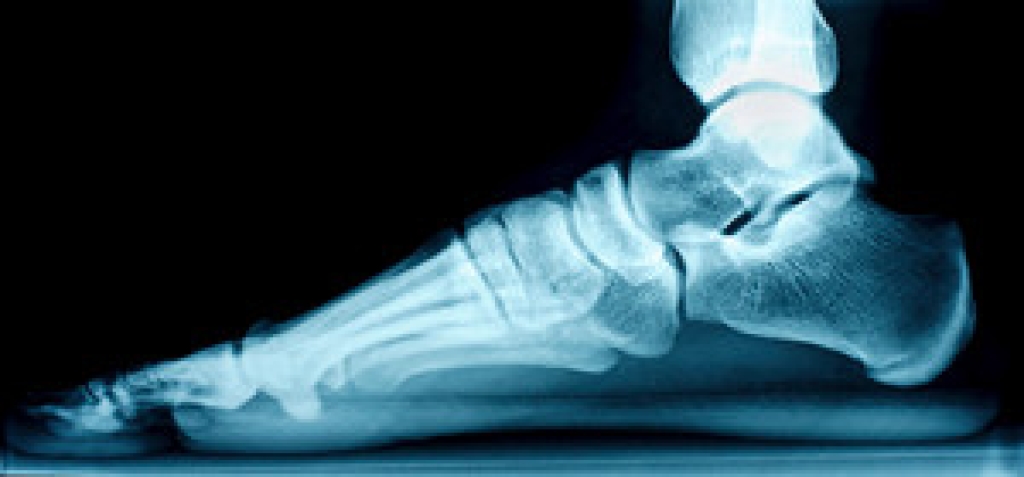

One problem that can occur is overpronation, which occurs when the arch of the foot flattens and tends to roll inward. This can cause pain and discomfort in your heels while you’re walking or even just standing up, trying to support your baby.